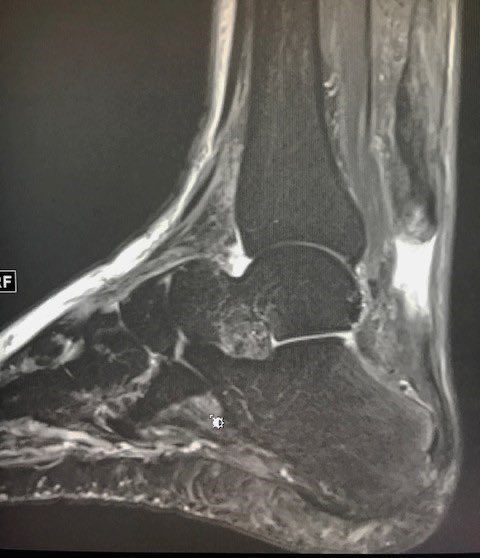

كيف يشخص التهاب #الوتر_العرقوبي ؟

يتم التشخيص عادة من خلال الفحص السريري من قبل الطبيب

و بناء على ذلك يحدد نوع الفحوصات اللازمة:

الأشعة العادية "السينية"✔️

الأشعة الصوتية✔️

أشعة الرنين المغناطيسي ✔️

.